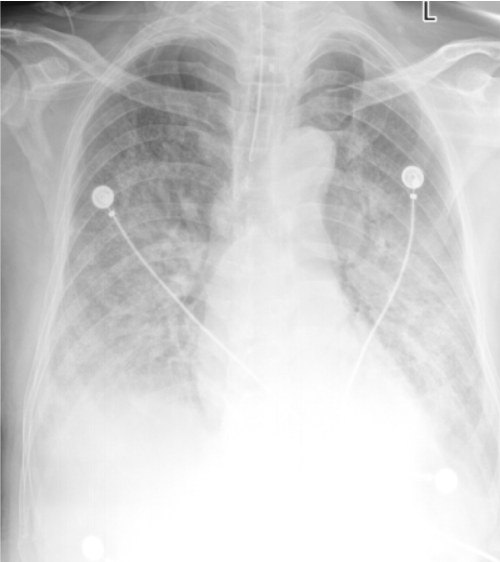

床旁胸片(2025-02-11):双肺纹理增多、模糊,双肺透亮度减低,见大片状密度增高影,考虑感染可能。双侧肋隔角显示不清,胸腔积液(图2)。

图2 患者入院后胸部X线片(2025-02-11)